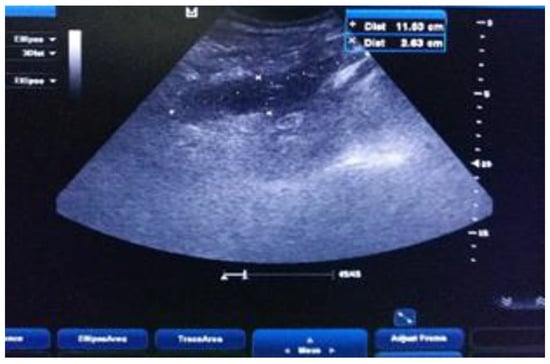

Case Presentation

- Imaging